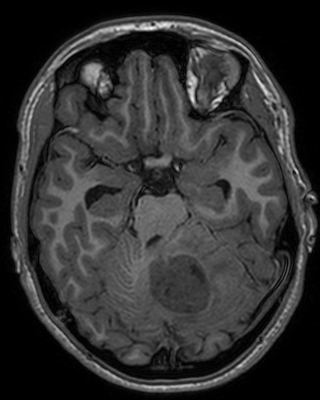

Refer to captionRefer to caption𝐱PCsubscript𝐱PC\mathbf{x}_{\mathrm{PC}}bold_x start_POSTSUBSCRIPT roman_PC end_POSTSUBSCRIPTRefer to captionRefer to caption𝐱LDsubscript𝐱LD\mathbf{x}_{\mathrm{LD}}bold_x start_POSTSUBSCRIPT roman_LD end_POSTSUBSCRIPTRefer to captionRefer to caption𝐱SDsubscript𝐱SD\mathbf{x}_{\mathrm{SD}}bold_x start_POSTSUBSCRIPT roman_SD end_POSTSUBSCRIPTRefer to captionRefer to captionAm-3D [14]Refer to captionRefer to captionPa-2.5D [8]Refer to captionRefer to caption𝐱^SDsubscript^𝐱SD\hat{\mathbf{x}}_{\mathrm{SD}}over^ start_ARG bold_x end_ARG start_POSTSUBSCRIPT roman_SD end_POSTSUBSCRIPT (ours)Refer to captionRefer to caption𝐱PCsubscript𝐱PC\mathbf{x}_{\mathrm{PC}}bold_x start_POSTSUBSCRIPT roman_PC end_POSTSUBSCRIPTRefer to captionRefer to caption𝐱LDsubscript𝐱LD\mathbf{x}_{\mathrm{LD}}bold_x start_POSTSUBSCRIPT roman_LD end_POSTSUBSCRIPTRefer to captionRefer to caption𝐱SDsubscript𝐱SD\mathbf{x}_{\mathrm{SD}}bold_x start_POSTSUBSCRIPT roman_SD end_POSTSUBSCRIPTRefer to captionRefer to captionAm-3D [14]Refer to captionRefer to captionPa-2.5D [8]Refer to captionRefer to caption𝐱^SDsubscript^𝐱SD\hat{\mathbf{x}}_{\mathrm{SD}}over^ start_ARG bold_x end_ARG start_POSTSUBSCRIPT roman_SD end_POSTSUBSCRIPT (ours)Refer to captionRefer to caption𝐱PCsubscript𝐱PC\mathbf{x}_{\mathrm{PC}}bold_x start_POSTSUBSCRIPT roman_PC end_POSTSUBSCRIPTRefer to captionRefer to caption𝐱LDsubscript𝐱LD\mathbf{x}_{\mathrm{LD}}bold_x start_POSTSUBSCRIPT roman_LD end_POSTSUBSCRIPTRefer to captionRefer to caption𝐱SDsubscript𝐱SD\mathbf{x}_{\mathrm{SD}}bold_x start_POSTSUBSCRIPT roman_SD end_POSTSUBSCRIPTRefer to captionRefer to captionAm-3D [14]Refer to captionRefer to captionPa-2.5D [8]Refer to captionRefer to caption𝐱^SDsubscript^𝐱SD\hat{\mathbf{x}}_{\mathrm{SD}}over^ start_ARG bold_x end_ARG start_POSTSUBSCRIPT roman_SD end_POSTSUBSCRIPT (ours)Refer to captionRefer to caption𝐱PCsubscript𝐱PC\mathbf{x}_{\mathrm{PC}}bold_x start_POSTSUBSCRIPT roman_PC end_POSTSUBSCRIPTRefer to captionRefer to caption𝐱LDsubscript𝐱LD\mathbf{x}_{\mathrm{LD}}bold_x start_POSTSUBSCRIPT roman_LD end_POSTSUBSCRIPTRefer to captionRefer to caption𝐱SDsubscript𝐱SD\mathbf{x}_{\mathrm{SD}}bold_x start_POSTSUBSCRIPT roman_SD end_POSTSUBSCRIPTRefer to captionRefer to captionAm-3D [14]Refer to captionRefer to captionPa-2.5D [8]Refer to captionRefer to caption𝐱^SDsubscript^𝐱SD\hat{\mathbf{x}}_{\mathrm{SD}}over^ start_ARG bold_x end_ARG start_POSTSUBSCRIPT roman_SD end_POSTSUBSCRIPT (ours)Refer to captionRefer to caption𝐱PCsubscript𝐱PC\mathbf{x}_{\mathrm{PC}}bold_x start_POSTSUBSCRIPT roman_PC end_POSTSUBSCRIPTRefer to captionRefer to caption𝐱LDsubscript𝐱LD\mathbf{x}_{\mathrm{LD}}bold_x start_POSTSUBSCRIPT roman_LD end_POSTSUBSCRIPTRefer to captionRefer to caption𝐱SDsubscript𝐱SD\mathbf{x}_{\mathrm{SD}}bold_x start_POSTSUBSCRIPT roman_SD end_POSTSUBSCRIPTRefer to captionRefer to captionAm-3D [14]Refer to captionRefer to captionPa-2.5D [8]Refer to captionRefer to caption𝐱^SDsubscript^𝐱SD\hat{\mathbf{x}}_{\mathrm{SD}}over^ start_ARG bold_x end_ARG start_POSTSUBSCRIPT roman_SD end_POSTSUBSCRIPT (ours)Refer to captionRefer to caption𝐱PCsubscript𝐱PC\mathbf{x}_{\mathrm{PC}}bold_x start_POSTSUBSCRIPT roman_PC end_POSTSUBSCRIPTRefer to captionRefer to caption𝐱LDsubscript𝐱LD\mathbf{x}_{\mathrm{LD}}bold_x start_POSTSUBSCRIPT roman_LD end_POSTSUBSCRIPTRefer to captionRefer to caption𝐱SDsubscript𝐱SD\mathbf{x}_{\mathrm{SD}}bold_x start_POSTSUBSCRIPT roman_SD end_POSTSUBSCRIPTRefer to captionRefer to captionAm-3D [14]Refer to captionRefer to captionPa-2.5D [8]Refer to captionRefer to caption𝐱^SDsubscript^𝐱SD\hat{\mathbf{x}}_{\mathrm{SD}}over^ start_ARG bold_x end_ARG start_POSTSUBSCRIPT roman_SD end_POSTSUBSCRIPT (ours)Refer to captionRefer to caption𝐱PCsubscript𝐱PC\mathbf{x}_{\mathrm{PC}}bold_x start_POSTSUBSCRIPT roman_PC end_POSTSUBSCRIPTRefer to captionRefer to caption𝐱LDsubscript𝐱LD\mathbf{x}_{\mathrm{LD}}bold_x start_POSTSUBSCRIPT roman_LD end_POSTSUBSCRIPTRefer to captionRefer to caption𝐱SDsubscript𝐱SD\mathbf{x}_{\mathrm{SD}}bold_x start_POSTSUBSCRIPT roman_SD end_POSTSUBSCRIPTRefer to captionRefer to captionAm-3D [14]Refer to captionRefer to captionPa-2.5D [8]Refer to captionRefer to caption𝐱^SDsubscript^𝐱SD\hat{\mathbf{x}}_{\mathrm{SD}}over^ start_ARG bold_x end_ARG start_POSTSUBSCRIPT roman_SD end_POSTSUBSCRIPT (ours)

Figure 5: Qualitative comparison for test samples of the SLD-METS dataset. The zooms highlight the metastasis location. By design, our approach adds the CE signal to the input image, thereby preserving its image quality. The input images at the top have the same resolution, while they strongly differ at the bottom. Thus, the image quality of our output 𝐱^SDsubscript^𝐱SD\hat{\mathbf{x}}_{\mathrm{SD}}over^ start_ARG bold_x end_ARG start_POSTSUBSCRIPT roman_SD end_POSTSUBSCRIPT is poor in the bottom row and decent in the top row.

The average mean and maximal relative enhancement across the 351351351351 lesions is listed in the c¯¯𝑐\overline{c}over¯ start_ARG italic_c end_ARG and c^^𝑐\widehat{c}over^ start_ARG italic_c end_ARG columns of Table 1. Our approach significantly improves the predicted CE strength compared to Am-3D and Pa-2.5D. Note that c¯¯𝑐\overline{c}over¯ start_ARG italic_c end_ARG is not only sensitive to the CE strength (as c^^𝑐\widehat{c}over^ start_ARG italic_c end_ARG), but also to a lesion’s internal morphology and border delineation. A qualitative comparison of a typical lesion is visualized in the zooms at the top row of Figure 5. While Am-3D struggles to predict the internal morphology of the lesions, the CE strength of Pa-2.5D is too low. In contrast, our approach predicts the right contrast strength, morphology, and boundary of the lesion.